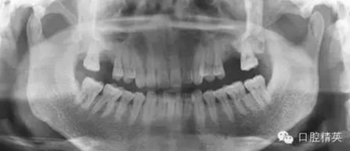

2。中觀察曲斷之所以沒顯示出牙槽骨皮質(zhì)和松質(zhì)骨密度明顯異常是因?yàn)樵摶疾款a舌冊皮質(zhì)骨密度正常,中間松質(zhì)骨密度減低的炎性陰影完全被正常皮質(zhì)骨影像覆蓋。

3。術(shù)前與患者溝通與問診不夠詳盡,沒有問及有無上頜竇炎病史。沒有仔細(xì)分析曲斷的左上頜竇的影響與右上頜竇仔細(xì)對比。也沒有分析患側(cè)上頜竇有無氣室化現(xiàn)象,術(shù)者考慮有所不周。